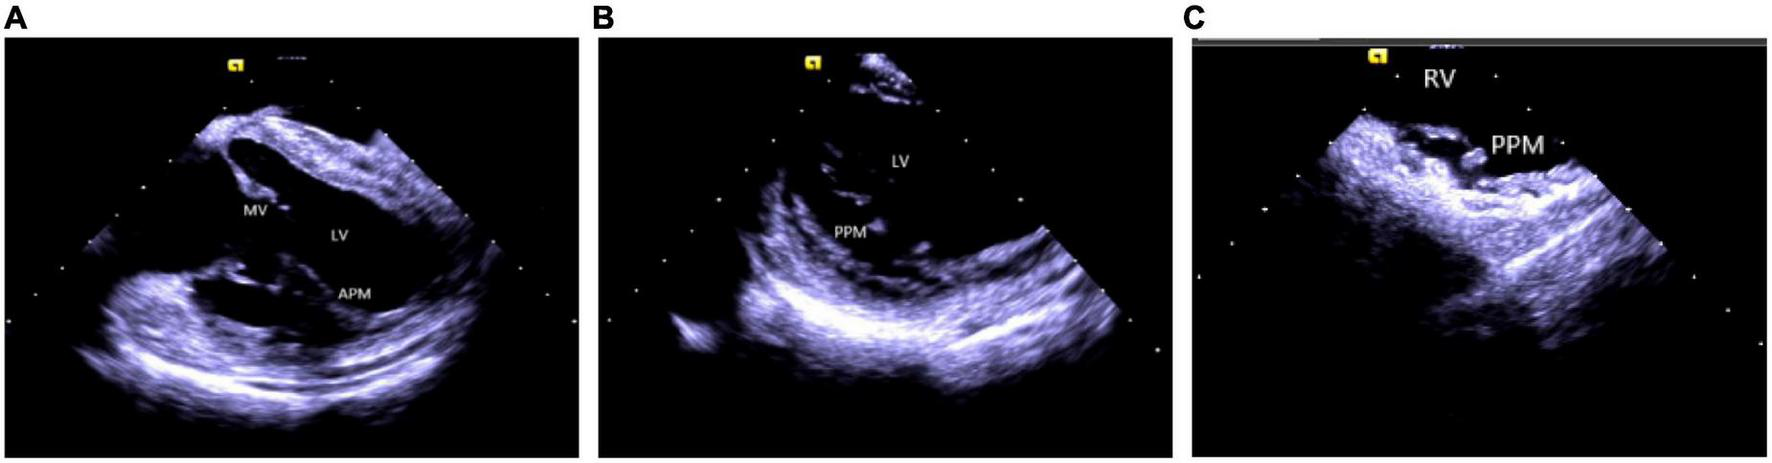

Catheter ablation is highly effective yet challenging because of complex PM anatomy, their independent movements during the cardiac cycles, the ambiguous origin of arrhythmias along with catheter-tissue contact instability. They were associated with a higher rate of local recurrence rate and had a lower success rate when compared with VA from other sites (32). Certain disadvantages of a 3D electroanatomical mapping system like the improper orientation of the catheter to the PM as well as operation of the catheter may sometimes lead to premature termination of arrhythmia and subsequent ablation failure (33). Integration of ICE with 3D electroanatomical mapping systems has further increased the efficacy of real-time monitoring of both catheter and local anatomy, along with accurate identification of the PMs structure (size, shape, and number of heads). An important factor governing a successful ablation is the appropriate contact between the ablation catheter and the targeted tissue, as well as the correct location and stability of the catheter tip for optimum outcome (1, 2, 34). A single-center study conducted on more than 100 people described that ICE effectively identifies the catheter’s location and lesion distribution segments, reduces the surgical time and radiation exposure, and thus, improves the overall success rate of surgery (35). Rivera et al. stated that CFS RF/ICE is the most effective way to reduce the consumption of antiarrhythmic drugs and dynamic ECG load after catheter ablation in LV papillary muscle origin arrhythmias (36). A strong correlation was also observed between the ICE usage and successful procedural outcomes, whereas the recurrence rate in patients undergoing ablation without ICE was 20 times higher than in ICE patients. Furthermore, ICE can duly identify abnormal PM echoes and the existence of scars, thus, recognizing the exact origin of arrhythmias (Figure 7).

FIGURE 7

Papillary muscle. (A) Left ventricular anterior papillary muscle. (B) Left ventricular posterior papillary muscle. (C) Right ventricular posterior papillary muscle. MV, mitral valve; LV, left ventricle; APM, anterior papillary muscle; PPM, posterior papillary muscle; RV, right ventricle.